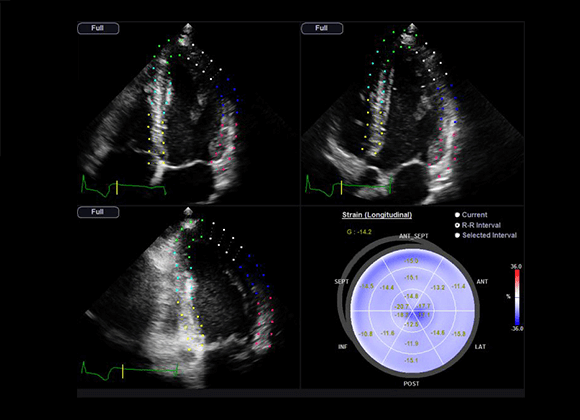

Strain+

Strain quantitatively displays a Bull's Eye which shows left ventricular motion and dyssynchrony at a glance.

Stress Echo

The Stress Echo package includes wall motion scoring and reporting. It includes exercise Stress Echo, pharmacologic Stress Echo, diastolic Stress Echo and free programmable Stress Echo.